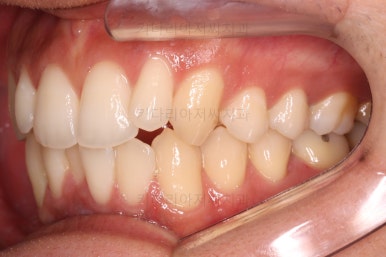

초진 시 입안의 모습입니다.

앞니가 약간 삐뚠 것 말고는 큰 문제는 없어보이네요.